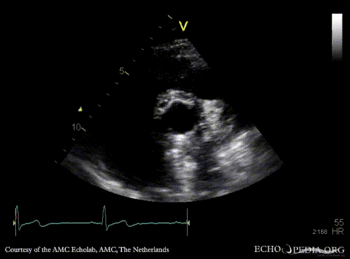

Bentall and aortic valve prosthesis

Courtesy of: AMC Echolab, AMC, The Netherlands

PLAX: aortic valve prosthesis and Bentall in situ PLAX with Color Doppler